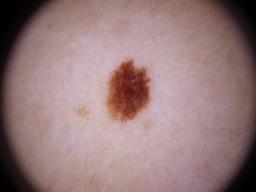

{

"age_approx": 70,

"anatom_site_general": "upper extremity",

"concomitant_biopsy": false,

"diagnosis_1": "Benign",

"diagnosis_2": "Benign melanocytic proliferations",

"diagnosis_3": "Nevus",

"diagnosis_confirm_type": "single image expert consensus",

"image_type": "dermoscopic",

"lesion_id": "IL_7986377",

"melanocytic": true,

"sex": "male"

}